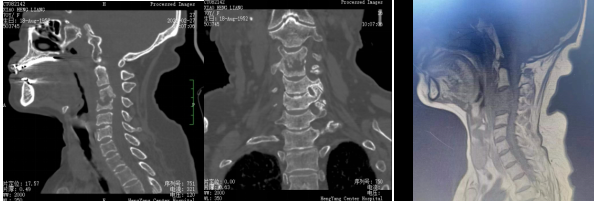

術(shù)前影像:C3、4椎體病變,椎管狹窄

患者入院后完善相關(guān)檢查,不查不知道,一查不簡單:患者頸椎疼痛不是簡單的肌肉勞損,而是頸椎骨頭出現(xiàn)了破壞、塌陷,神經(jīng)受壓。由于患者頸椎病變位置較高,骨質(zhì)破壞范圍較大,并后凸、脊髓受壓,椎體穩(wěn)定性差,稍有不慎容易出現(xiàn)災(zāi)難性后果?,F(xiàn)有的重建材料難以達到好的臨床效果,蘇光輝主任團隊采用先進的3D打印技術(shù),為患者進行了個性化手術(shù)方案及假體設(shè)計,假體與需要切除骨質(zhì)完美匹配,最大程度恢復(fù)解剖結(jié)構(gòu)及重建的穩(wěn)定性,對假體進行骨小梁結(jié)構(gòu)設(shè)計,具有良好的骨長入效果,能夠減少假體下沉及松脫等術(shù)后并發(fā)癥的發(fā)生。